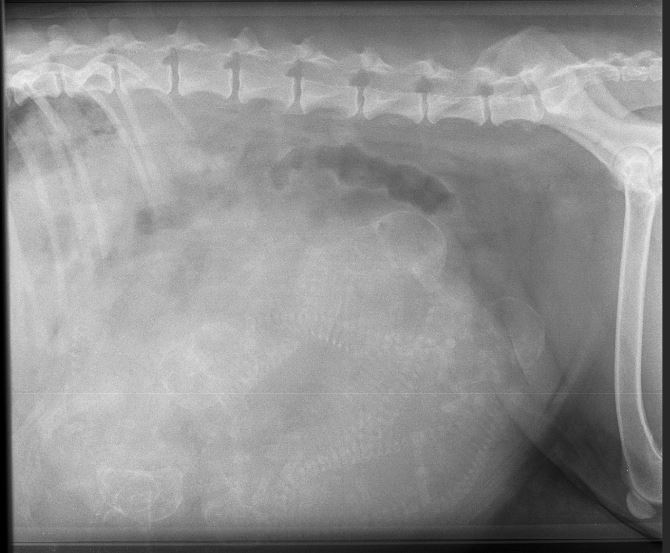

Morgens um 6:25 Uhr begann es, aber eigentlich begann es ja schon am Vorabend, an Mamas 63. Trächtigkeitstag. Da waren Frauchen und Herrchen mit Mama nämlich nochmal beim Tierarzt. Der hat nachgeschaut, wieviele wir denn jetzt eigentlich genau sind. Wir selbst wussten es ja, aber alle anderen gingen bis dahin von drei bis vier Babys aus, weil das der Tierarzt beim Ultraschall gesehen hatte. Aber Mamas Bauchumfang sagte etwas ganz anderes und daher wurde sie geröntgt.

Na die haben aber dumm aus der Wäsche geschaut, als sie das Röntgenbild (siehe unten auf der Seite) sahen und lustiges Wirbelsäulenzählen spielten. Sechs fanden sie. Oder sieben? Oder gar acht? Und dann warteten sie.

Mamas Röntgenbild:

Zum Vergrößern anklicken